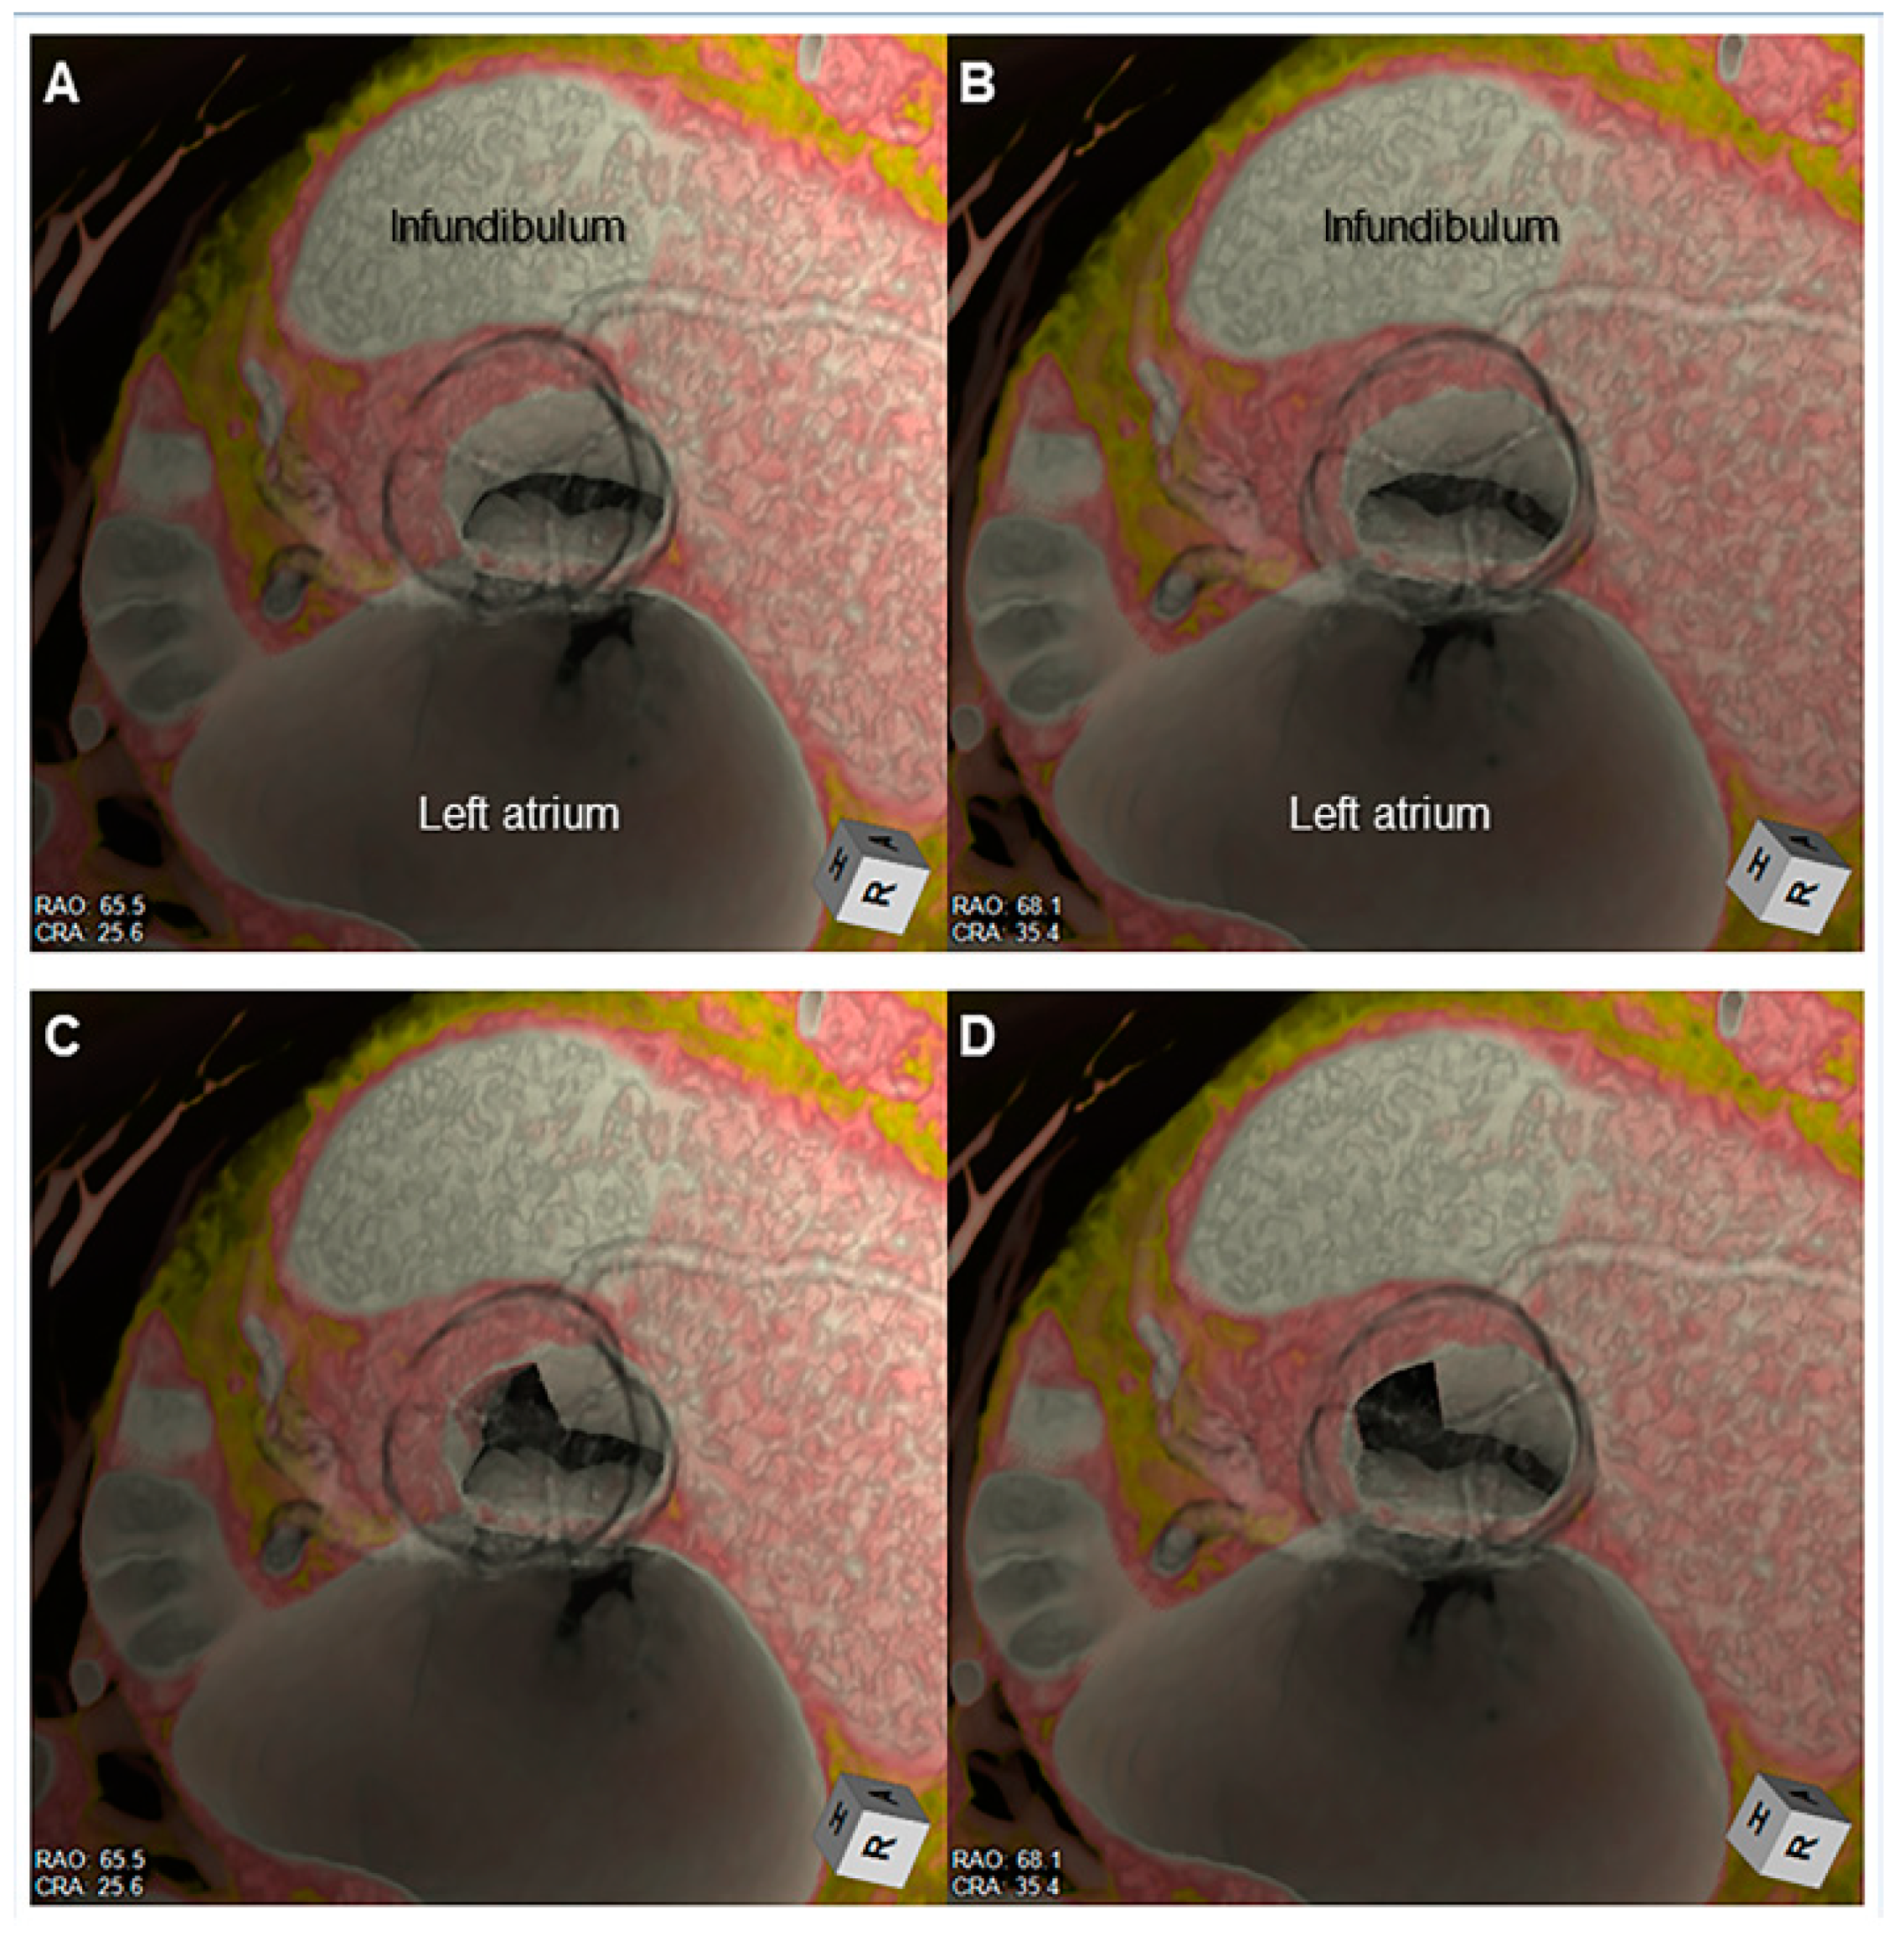

- Right ventricular outflow tract obstruction in repaired tetralogy of Fallot to guide transcatheter pulmonary valve replacement (Figure 16).